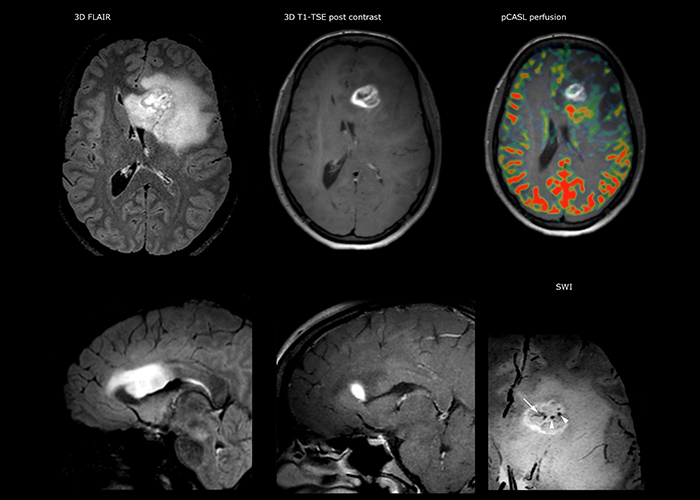

“The biggest challenges are properly characterizing the lesion and giving the surgeon all the information needed, such as the location of vessels and functional areas. Sometimes a very comprehensive exam is necessary, such as when a mass has been discovered at another hospital after which the patient is referred to us. We then do both lesion characterization and preoperative imaging in one exam, so both morphologic and functional assessment. For morphologic assessment we will use pre- and post-contrast T1-weighted imaging, FLAIR to assess infiltration, and diffusion. For functional characterization we will perform perfusion, spectroscopy, and susceptibility weighted imaging to look for micro vessels or micro hemorrhage inside the lesion[4]. For preoperative imaging we perform specific morphologic imaging that is compatible with the navigation system; depending on the location of the tumor, we would do fMRI or DTI.”